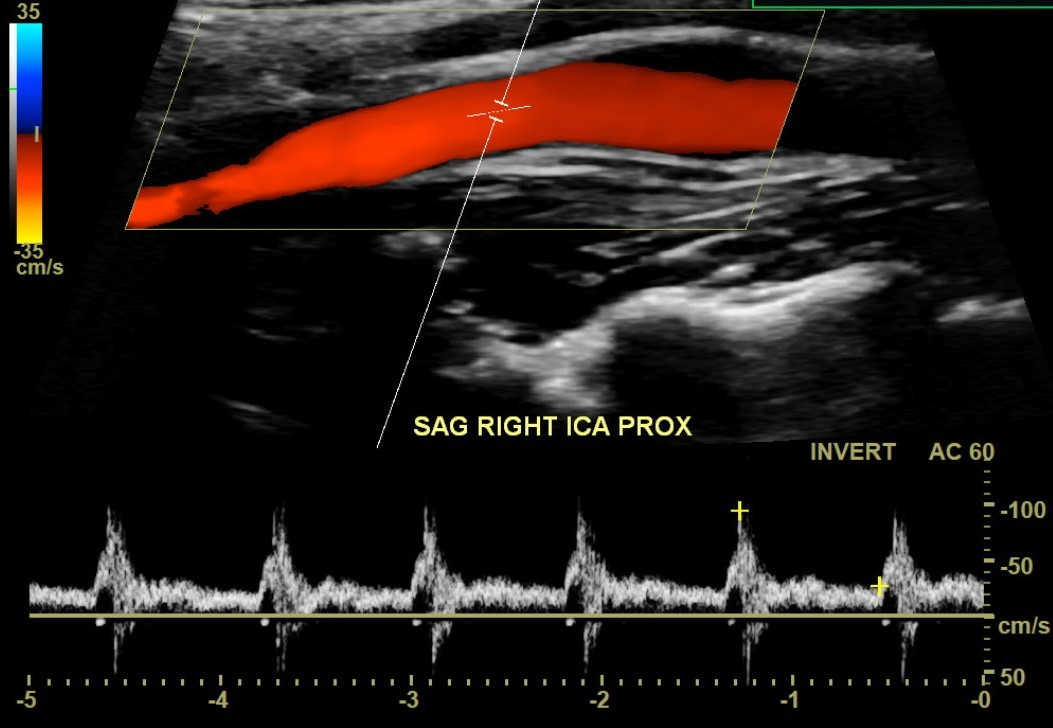

Once a bruit is heard, carotid artery imaging is the next step. The obvious first option should be a carotid artery ultrasound. Most appropriate use criteria define a bruit as a legitimate reason for the ultrasound. The ultrasound will usually be able to show stenosis if it is present.